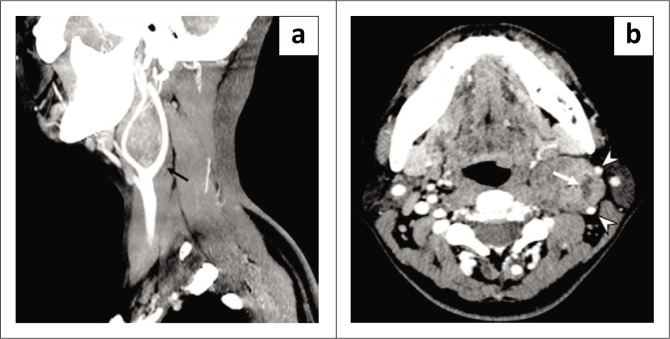

Nerve sheath tumours of the sympathetic chain are extremely rare and present a diagnostic challenge. A 42-year-old female presented with asymptomatic left cervical swelling. Imaging with sonography, CT, MR and angiography demonstrated a lesion splaying the carotid bifurcation, the lyre sign. Following surgical excision, histology revealed a schwannoma. Imaging features of carotid body tumours and parapharyngeal schwannomas can be similar, as both can cause splaying of the carotid bifurcation. The differential diagnosis of such tumours and their management are discussed.

Contribution: This article highlights another cause of the lyre sign on radiological imaging besides carotid body tumours.